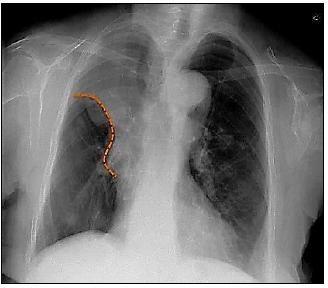

Um raio-x de tórax apresenta um achado que foi marcado com a linha pontilhada. Observe:

Acerca da imagem anterior, assinale a afirmativa correta.